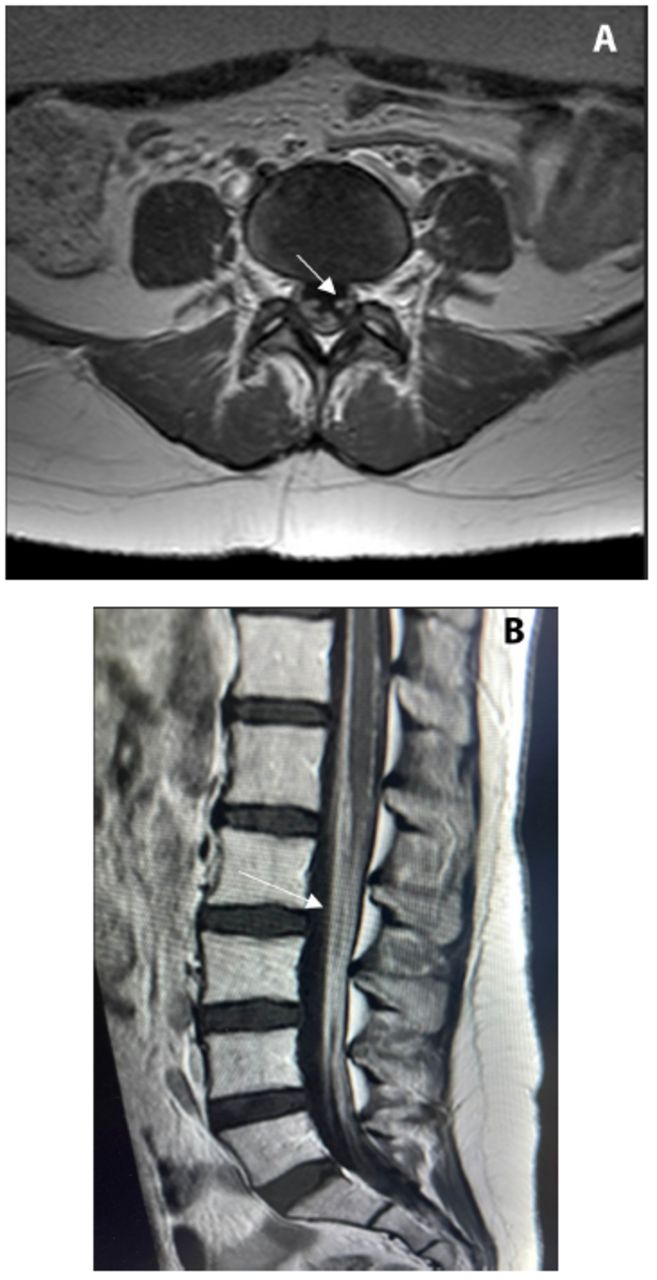

Nonenhanced magnetic resonance imaging (MRI) of the brain revealed normal findings. Enhanced MRI of the lumbosacral plexus showed abnormal diffuse enhancement of the lumbar intradural nerve root in the cauda equina as shown in Pictures figures 1a and 12b, without vertebral body or disc enhancement and epidural or paraspinal collection.

- Enhanced MRI of the lumbosacral plexus showing abnormal diffuse enhancement of the lumbar intradural nerve root in the cauda equina, with no vertebral body or disc enhancement, and no epidural or paraspinal collection.

Neurobrucellosis can be diagnosed by fulfilling specific diagnostic criteria as outlined in various studies. In one approach, the criteria were: the presence of neurological symptoms and signs that could not be explained by other diseases, positive agglutination titer for Brucella in blood greater than 1:160, presence of pleocytosis in the CSF if patient received no treatment, and notable clinical improvement following appropriate therapy.7 Another approach for diagnosing neurobrucellosis among patients with laboratory-confirmed brucellosis involves the presence of at least one of the following criteria: symptoms and signs suggestive of neurobrucellosis, isolation of Brucella species from CSF and/or the presence of anti-Brucella antibodies in the CSF, evidence of lymphocytosis, increased protein levels, and decreased glucose levels in the CSF, or abnormal findings on cranial MRI or computed tomography (CT).8 In our case, the patient met several diagnostic criteria for neurobrucellosis. Her findings showed a highly positive Brucella abortus screening titer by ELISA and a high IgG ratio. CSF analysis revealed a high WBC count with lymphocytosis, a high protein level, and a normal glucose level. Blood culture was positive for Brucella melitensis, whereas the CSF culture was negative. These findings closely align with the diagnostic criteria outlined in both approaches. Non-enhanced MRI of the brain revealed normal findings, which is consistent with some cases of neurobrucellosis where cranial MRI does not show abnormalities. Highlighting that no contrast was used in the MRI of our case is important, which may influence the detection of abnormalities. However, enhanced MRI of the lumbosacral plexus showed abnormal diffuse enhancement of the lumbar intradural nerve roots in the cauda equina. The correlation between our case and the referenced diagnostic criteria underscores the complexity of diagnosing neurobrucellosis and highlights the importance of comprehensive diagnostic workups. This includes serological tests, CSF analysis, and advanced imaging techniques to ensure accurate diagnosis and appropriate treatment.

The pathogenesis of the disease involves both immunological mechanisms and direct invasion, leading to the demyelination of the white matter, spinal cord, and peripheral nerves of the brain. This results in various peripheral manifestations such as myelopathy, radiculopathy, or polyradiculopathy, which typically affect the legs more than the hands.9 The clinical manifestation in our case aligns with these findings, as our patient exhibited progressive symmetrical weakness in the lower limbs. Additionally, the NCS did not indicate signs of large-fiber neuropathy, which could be attributed to the unavailability of electromyography at the time of evaluation. This limitation underscores the necessity for alternative diagnostic approaches. Consequently, the identification of root enhancement in MRI findings becomes particularly critical. In our patient, MRI revealed abnormal diffuse enhancement of the lumbar intradural nerve roots in the cauda equina. This finding is indicative of inflammation or infection of the nerve roots, which could correlate with the pathophysiological process of demyelination seen in neurobrucellosis.